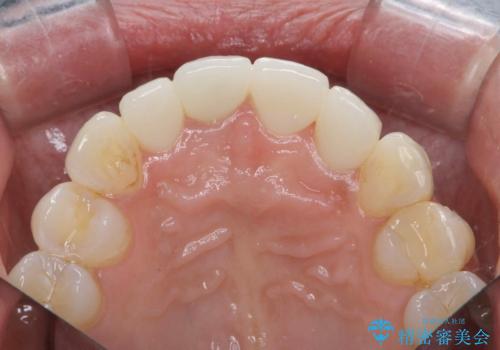

金属色の見える前歯 オールセラミックで審美治療

- 前歯のクラウンの見た目が不自然、歯の根元が見えたり金属色が気になるので改善したい、とセラミック治療を希望され来院されました。

歯肉の位置変化による審美障害を改善するため、オールセラミックジルコニアクラウンで再治療を行い審美性の改善を計画します。

見た目が自然になり、色調も天然の歯とおなじような透明感のある色調が再現され、大変喜んでいただくことができました。